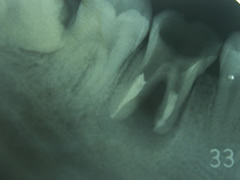

チャート8

はい、奥歯に支える歯が無くなってしまいました。この欠損状態ですと、ホケン治療ではどうしても「入れ歯」を選択しなくてはなりません。

チャート9

あらら、、反対側も同じような運命だったのですね。

※チャート8の方の全景です。